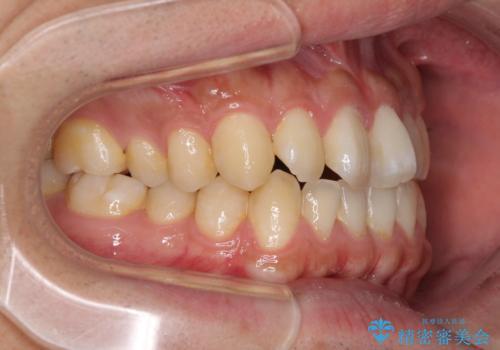

前歯のみの矯正治療を希望でしたが、上顎臼歯が舌側転位していたため、上顎は全体を、下顎は前歯のみを矯正治療することとしました。

矯正治療は上下全顎を行うことが大前提ですが、費用などの点から、今回は部分矯正を選択することとなりました。

患者様本人は咬みにくさを感じていないようですが、部分矯正は咬み合わせの改善が困難であることが多く、咬みにくさが残ることがあります。